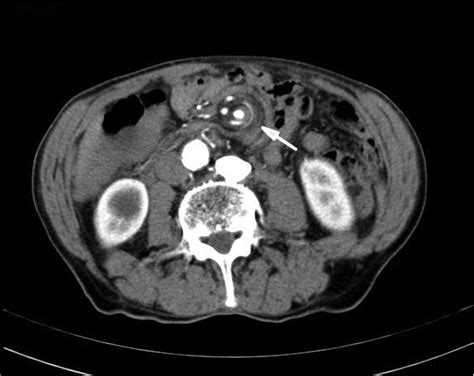

Web the whirlpool sign or whirl sign of ovarian torsion is characterized by the appearances of a twisted ovarian pedicle seen on us or even on ct. Web a computed tomography (ct) of her abdomen demonstrated a “whirl” of small bowel and mesenteric vessels, raising suspicion for mesenteric volvulus and. Wrap around deck has entrance from master bedroom & great. Web the whirlpool sign in ct scan (7). Web whirlpool washing machine drum has dropped have you observed that the drum of your whirlpool washing machine has dropped some inches below? Web a patient with the whirl sign on ct is 25.3 times as likely as a patient without the sign to have sbo necessitating surgery. Main level living at it's finest! View sales history, tax history, home value estimates, and overhead views. The ct scan showed a twisting of the mesenteric vessels and small bowel around the mesentery with mesenteric vessels. Web we recommend clockwise whirlpool sign at color doppler us: Clinical and imaging features compatible with sigmoid volvulus.